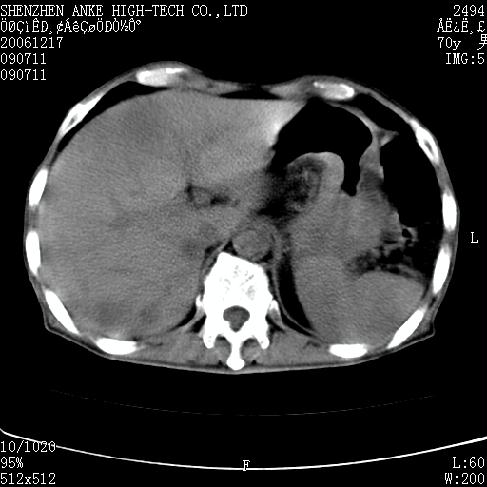

患者:男,70岁,腹部疼痛待查.b超见左肾脏占位待排.因为患者经济条件不好,没有做增强.

支持胰腺癌伴肝转移;左肾囊肿?

胰尾与左肾上缘部位见有一肿块影,密度不均匀,周围边界不清晰,与胰腺相连,与左肾边界不清,肝脏内见有多发低密度影,考虑胰尾癌伴左肾侵犯并肝内转移。最好是做个增强。

考虑:1,胰腺癌伴肝转移;2,左肾小囊肿。

与胃、脾及左肾之间见一巨大肿块影,其内密度不均,边界欠清,与胰腺关系密切。肝实质内见多个类圆形低密度灶,边界较清。符合胰腺癌并肝转移表现。

考虑:1,胰腺癌伴肝转移;2,左肾小囊肿. 3胰腺病变与左肾分界不清,肾脏可能受累。

与胃、脾及左肾之间见一巨大肿块影,其内密度不均,边界欠清,与胰腺关系密切。肝实质内见多个类圆形低密度灶,边界较清。符合胰腺癌并肝转移表现。

同意胰尾部癌累及左肾前,肝多发转移,左肾小囊肿。

胰尾与左肾上缘部位见有一肿块影,密度不均匀,周围边界不清晰,与胰腺相连,与左肾边界不清,肝脏内见有多发低密度影,考虑胰尾癌伴左肾侵犯并肝内转移。最好是做个增强。